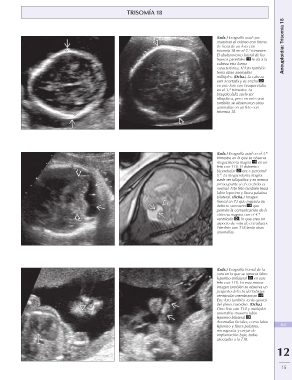

(Izda.) Ecografía axial que Aneuploidía: Trisomía 18

muestran el cráneo con forma

de fresa de un feto con

trisomía 18 en el 2.º trimestre.

El abultamiento lateral de los

huesos parietales le da a la

cabeza esta forma

característica. El feto también

tenía otras anomalías

múltiples. (Dcha.) La cabeza

está acortada y es ancha

en este feto con braquicefalia

en el 3.er trimestre. La

braquicefalia suele ser

idiopática, pero en este caso

también se observaron otras

anomalías en un feto con

trisomía 18.

(Izda.) Ecografía axial en el 3.er

trimestre en la que se observa

megacisterna magna en un

feto con T18. El diámetro

bicerebelar era < percentil

5.º. La megacisterna magna

suele ser idiopática y es menos

preocupante si el cerebelo es

normal. Este feto también tenía

labio leporino y fisura palatina

bilateral. (Dcha.) Imagen

frontal en T2 que muestra un

defecto vermiano que

permite la comunicación de la

cisterna magma con el 4.º

ventrículo , lo que crea un

aspecto de «ojo de cerradura».

Este feto con T18 tenía otras

anomalías.

(Izda.) Ecografía frontal de la 837

cara en la que se aprecia labio

leporino unilateral en este 12

feto con T18. En esta misma

imagen también se observa un

pequeño defecto del tabique

ventricular membranoso .

Este feto también tenía quistes

del plexo coroideo. (Dcha.)

Otro feto con T18 y múltiples

anomalías muestra labio

leporino bilateral .

Anomalías faciales, como labio

leporino y fisura palatina,

micrognatia y orejas de

implantación baja, todas

asociadas a la T18.